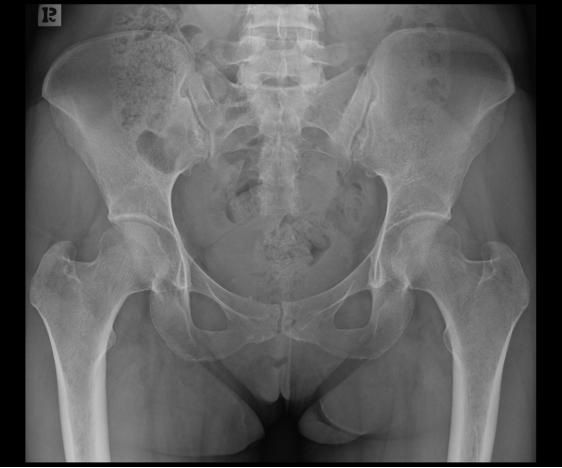

X线检查:

由于此病多由老年人骨质疏松症导致骶骨骨折,很多老年患者这种腰痛常常会被误诊为其他腰痛的原因,如,椎间盘突出/腰肌劳损等。此外,这种骨折通过骨盆 X 线平片很难发现骶骨骨折;特别是骶骨轻微移位的不全骨折大多无法判断。故诊断这种骨折的最佳方式是CT+磁共振检查。

2、单侧或双侧骶骨翼骨皮质断裂,见迂曲纵行骨折线,大致与骶髂关节平行(双侧多见);

3、骶骨体部看见骨折线

4、冠状位上述骨折形成 “H”型 ,故有人称东风本田征(为了方便记忆)

5、骨折线一般较为模糊,看见看到骨质硬化;